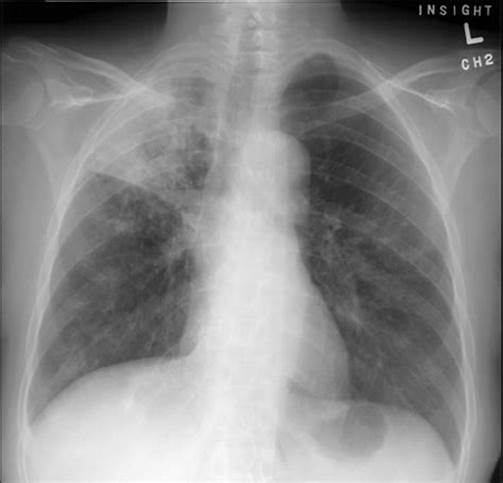

- 胸部影像学检查显示与活动性肺结核相符的病变。

- 胸部影像学显示与活动性肺结核相符的病变,患者有咳嗽、咳痰、咯血等肺结核的可疑症状。

- 胸部影像学检查显示与活动性肺结核相符的病变,PPT试验强阳性或γ-干扰素释放试验(又叫T-SPOT)阳性。

- 胸部影像学检查显示与活动性肺结核相符的病变,经过诊断性抗菌治疗两周无效,或随访检查可以排除其他原因导致的肺部疾病者。

肺结核诊断的直接依据是找到结核分枝杆菌,如果找不到细菌,要依靠流行病学、临床表现,再结合医生的临床经验来综合判断。

如果实在难以做出诊断,还可以诊断性的治疗和抗结核治疗,通过治疗的反应来判断和修正原来的诊断。